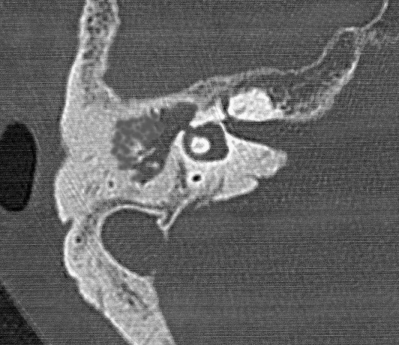

既往歴と家族歴とに特記すべきことはない。血液所見に異常を認めない。神経学的所見に異常を認めない。右鼓膜の写真と右側頭骨CTとを別に示す。